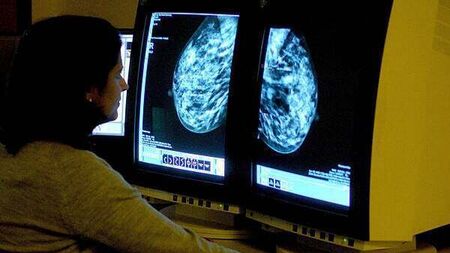

BreastCheck provides a breast cancer screening service every two years for women aged 50-69 at a clinic or at one of 24 mobile screening units.

The first breast screening invitation is usually issued within two years of a woman’s 50th birthday, and the results of the mammogram are usually issued within three weeks.